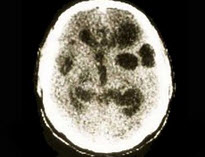

参考下图,猪囊尾蚴寄生于人脑部可引起脑囊尾蚴病。依据临床表现的不同,脑囊尾蚴病可以分为( )

A、脑实质型

B、脑室型

C、软脑膜型

D、小脑型

E、脊髓型